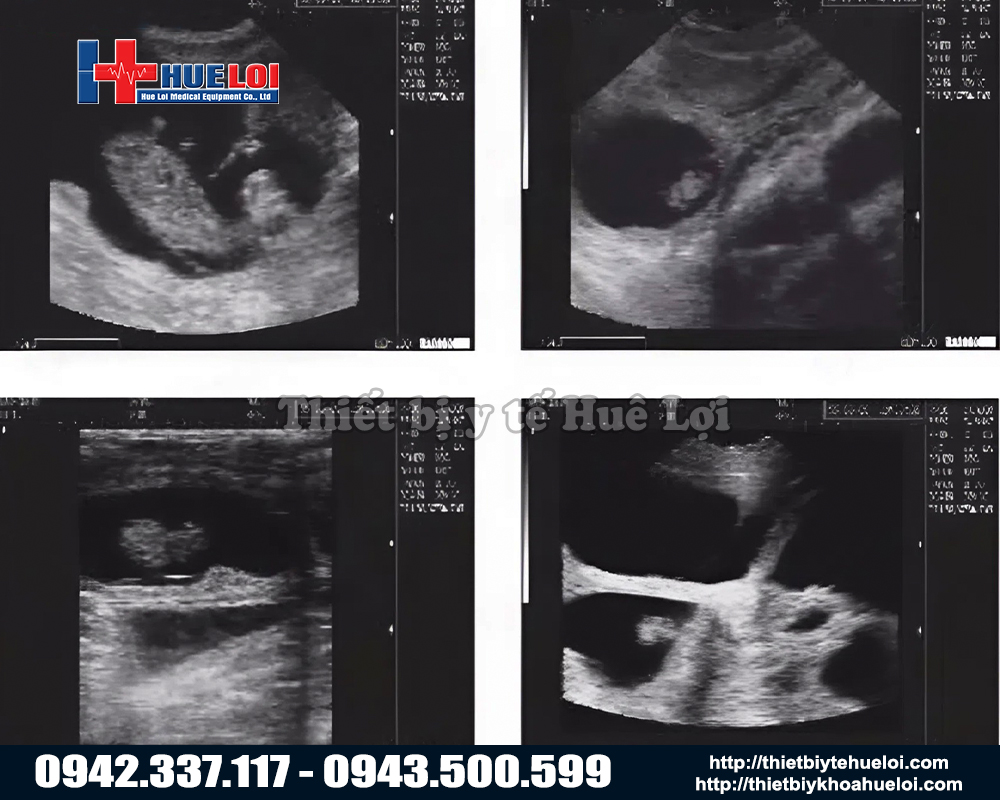

Máy siêu âm xách tay WELL.D M3V là giải pháp chẩn đoán thai và đo độ dày mỡ lưng di động hàng đầu, được thiết kế chuyên biệt cho ngành chăn nuôi lợn hiện đại. Máy sử dụng công nghệ sóng âm tần số cao, thiết bị cho phép tầm soát thai sản và kiểm tra nội tạng một cách an toàn, chính xác và hoàn toàn không xâm lấn. Với kết cấu bền bỉ, nhỏ gọn cùng pin sạc tiện dụng, M3V đóng vai trò như một 'phòng khám di động', hỗ trợ bác sĩ thú y đưa ra kết quả tức thì ngay tại chuồng trại mà không cần di chuyển vật nuôi.

Nhờ công nghệ hình ảnh "Mimage" sắc nét, M3V giúp phát hiện thai sớm và chính xác, loại bỏ ngay những nái không mang thai (lốc, sảy), giúp trại tiết kiệm hàng triệu đồng tiền cám nuôi báo cô mỗi ngày.

Dù là máy cầm tay nhỏ gọn, M3V được trang bị nền tảng siêu âm y tế với công nghệ hình ảnh "Mimage", mang lại chất lượng hình ảnh chẩn đoán sắc nét và rõ ràng đáng kinh ngạc. Với màn hình LCD 7 inch lớn so với các dòng cầm tay (thường chỉ 5-5.5 inch). Tỷ lệ 16:9 giúp việc quan sát các chi tiết nhỏ trở nên dễ dàng hơn bao giờ hết.